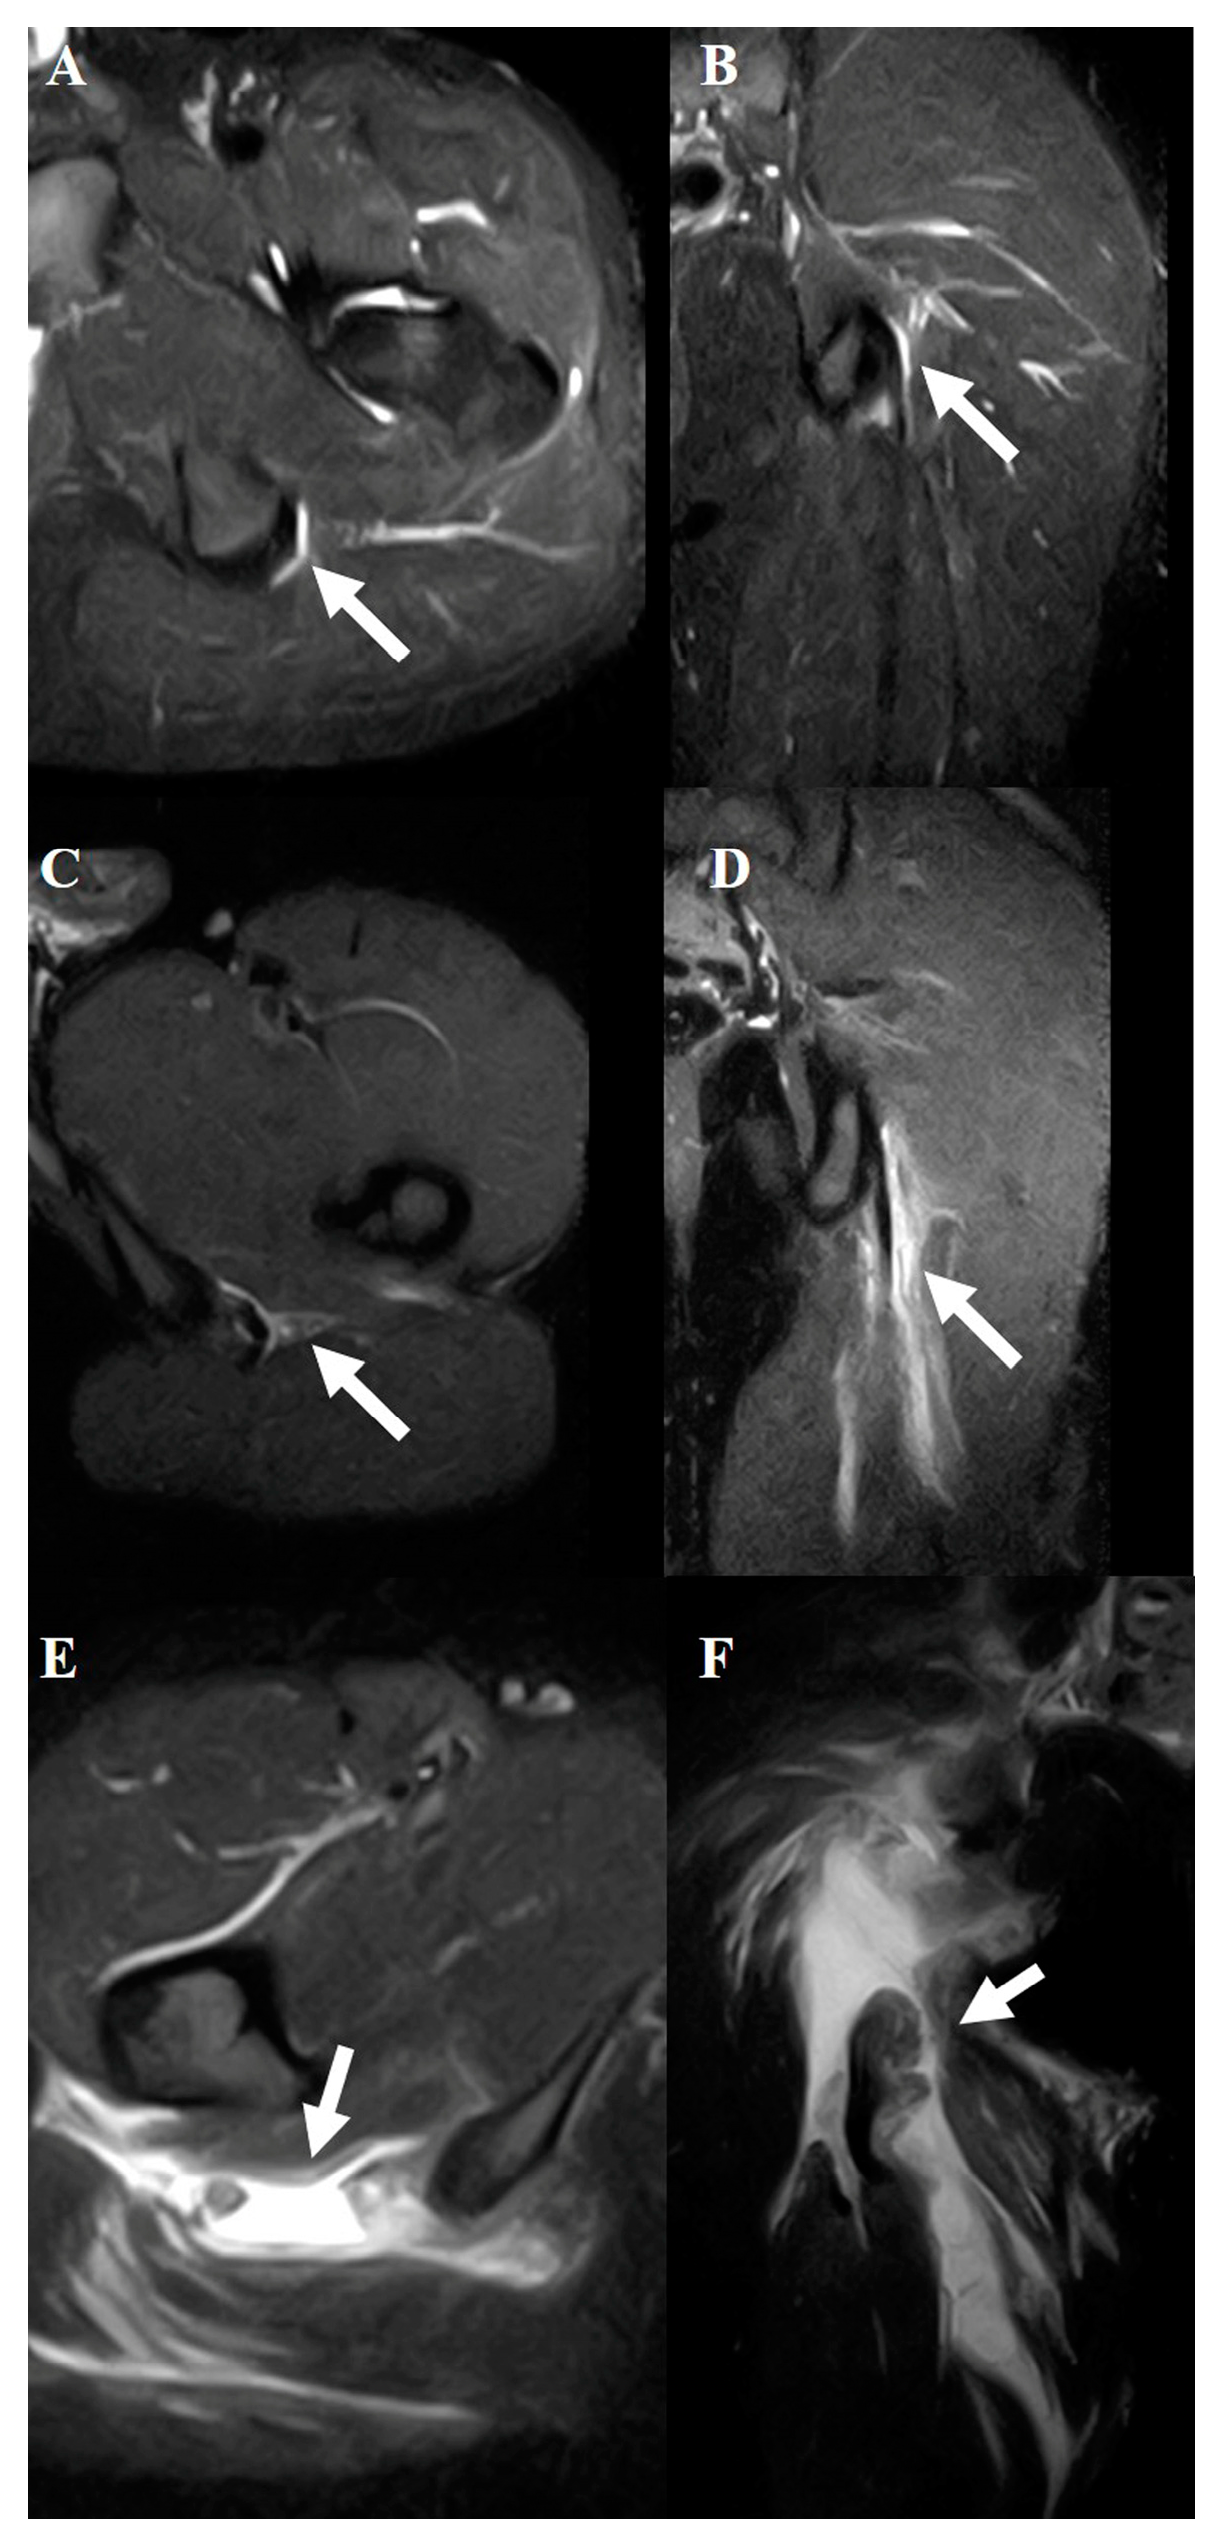

2.4. Hamstring Muscle Diagnosis Using MRI